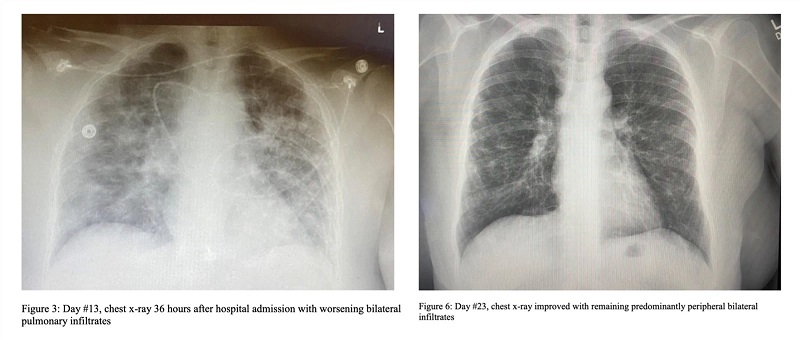

After receiving NMN cocktail therapy (right), the patient's lung condition improved significantly

Like NMN cocktail therapy, it has reversed the storm of cellular inflammatory factors in clinical treatment and helped patients with severe new coronary pneumonia after 10 days of treatment.

Recovered and discharged.

The treatment also improved symptoms such as fever, chest pressure, cough, headache and lack of energy in many patients.